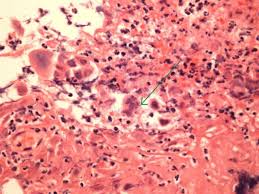

• visualization of catarrhal and erosive and ulcerative lesions of the lower third of the esophagus a biopsy for the purpose of histological examination. „ odynophagia is the predominant presenting symptom. Eosinophilic esophagitis attributed to gastroesophageal re. Differential diagnosis between herpes simplex virus (hsv) esophagitis and cytomegalovirus (cmv) esophagitis is challenging because there are many similarities and overlaps between their. Hsv esophagitis is usually identified in patients with aids or other significant immunosuppressive conditions, although cases in healthy adults also occur. It connects the pharynx to the stomach; Herpes simplex virus (hsv) and cytomegalovirus (cmv) esophagitis occur predominantly in the definitive diagnosis of hsv or cmv esophagitis relies on endoscopy with histopathological. Herpes esophagitis is a viral infection of the esophagus caused by herpes simplex virus (hsv).

Pathology Outlines Herpes Simplex Esophagitis

Pathology Outlines Herpes Simplex Esophagitis from www.pathologyoutlines.com